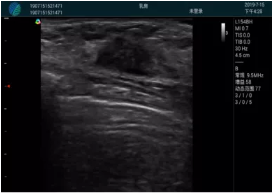

M20實(shí)時(shí)引導(dǎo):向包塊后方間隙注射利多卡因

清晰顯示腺體內(nèi)低回聲快影,邊界清晰,包膜較光滑

確定進(jìn)針路徑并實(shí)時(shí)監(jiān)測抽吸針與腫塊位置關(guān)系

抽吸針進(jìn)入腫塊內(nèi)部進(jìn)行旋切

抽吸過程中可見腫塊明顯縮小,并根據(jù)腫塊位置改變針道位置

抽吸旋切后再進(jìn)行超聲復(fù)查,原腫塊區(qū)域未見殘留組織及出血